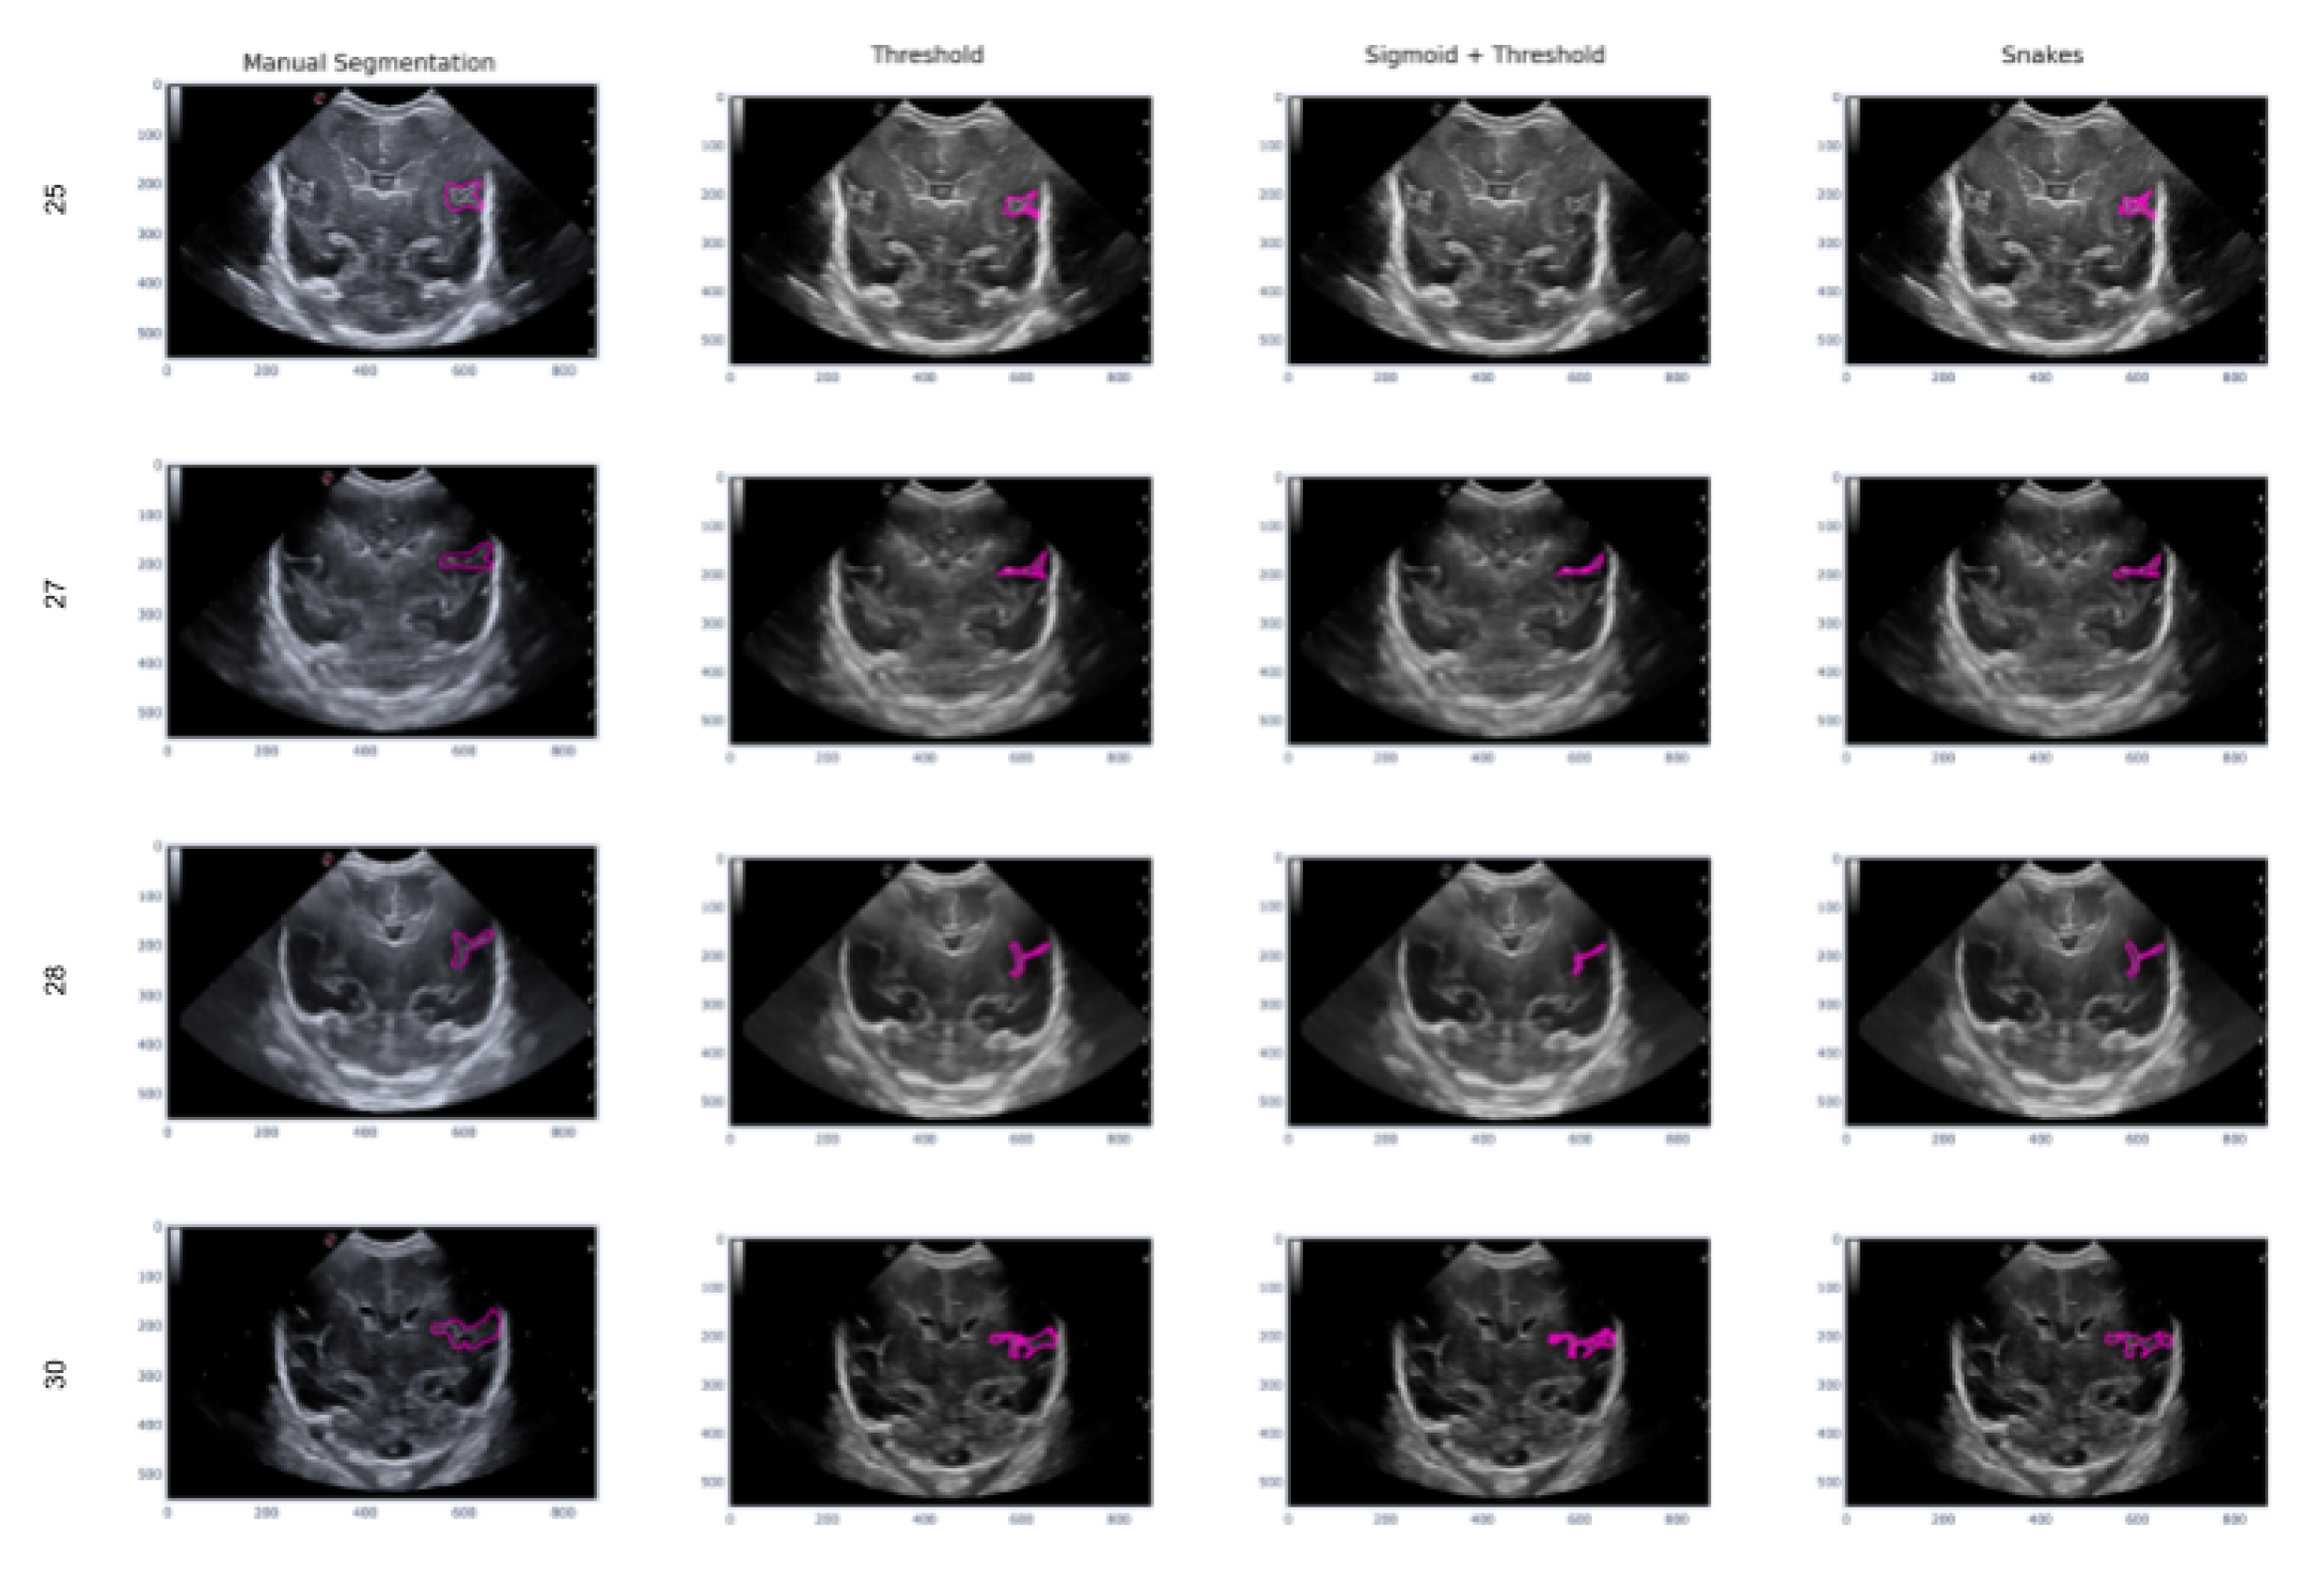

In this second scenario, we will analyze the segmentation results of the different methods applied to the Sylvian furrow at four different weeks of gestation (week 25, 27, 28, and 30) in various infants. Our aim here is to investigate how the noise present in ultrasound images affects the performance of the segmentation algorithms across different cases.

In the first row of Figure 17, it was observed that the Sigmoid + Threshold method failed to segment the groove, while the Threshold and Snakes methods were successful, but only if the groove was well defined. In the subsequent rows, which corresponded to weeks 27, 28, and 30 of gestation, a clear difference was observed between the methods that utilized the Threshold (Threshold and Sigmoid + Threshold). The Sigmoid + Threshold method was found to be more sensitive and faithful in segmenting the furrow, but lost precision when defining its shape. On the other hand, the Threshold method lost precision during segmentation but improved the definition of the furrow’s shape.

Another notable observation from the figure is the difference in the way the methods perform segmentation. Specifically, the Snake method produces smoother segmentation results, which appear to be more regular and follow the shape of the groove more accurately. In contrast, when the Threshold method is applied, the segmentation result is more irregular and abrupt, with small peaks visible in the defined shape of the groove.

Finally, it is evident that in some instances where the groove is more affected by noise, particularly during weeks 27 and 28, the Sigmoid preprocessing can lead to the loss of information about the groove’s shape, resulting in a failure to segment part of it using this method.

Figure 17. Segmentation of the sylvian sulcus applying the three defined segmentation methods (Threshold, Sigmoid + Threshold and Sankes) for differents babies and weeks